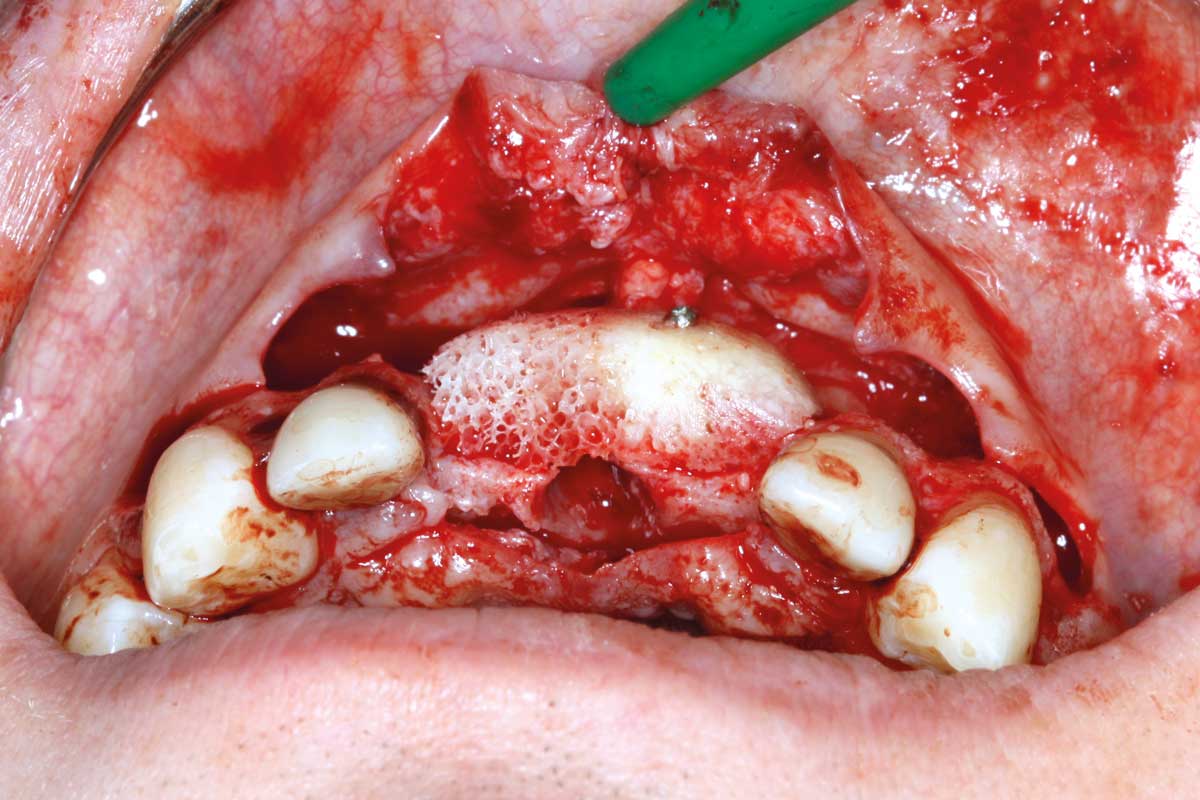

05/26 - Positioning of maxgraft® bonebuilder

Ridge augmentation in the maxilla with maxgraft® bonebuilder in the aesthetic zone - Dr. M. Kristensen